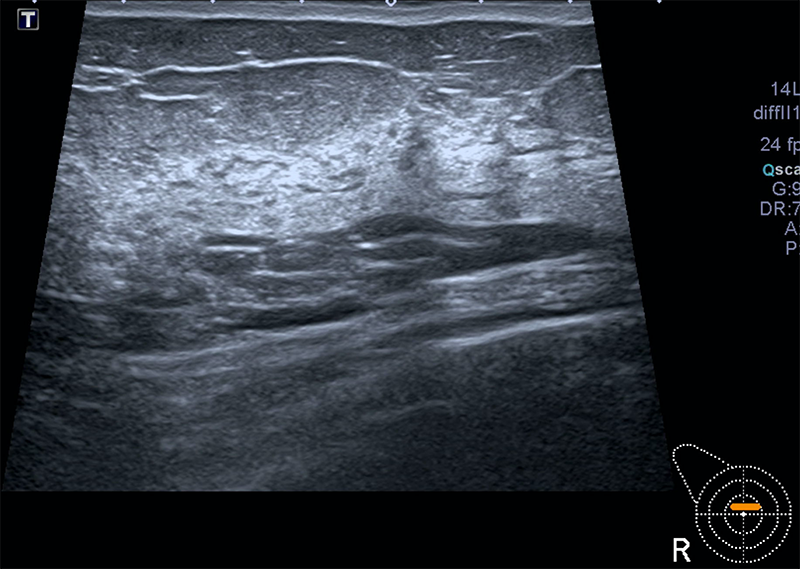

- l’échographie mammaire : il s’agit d’un outil d’imagerie explorant la région mammaire en utilisant les ultrasons. Elle est complémentaire de la mammographie.

- pour l’échographie: vous serez installée sur la table d’examen.